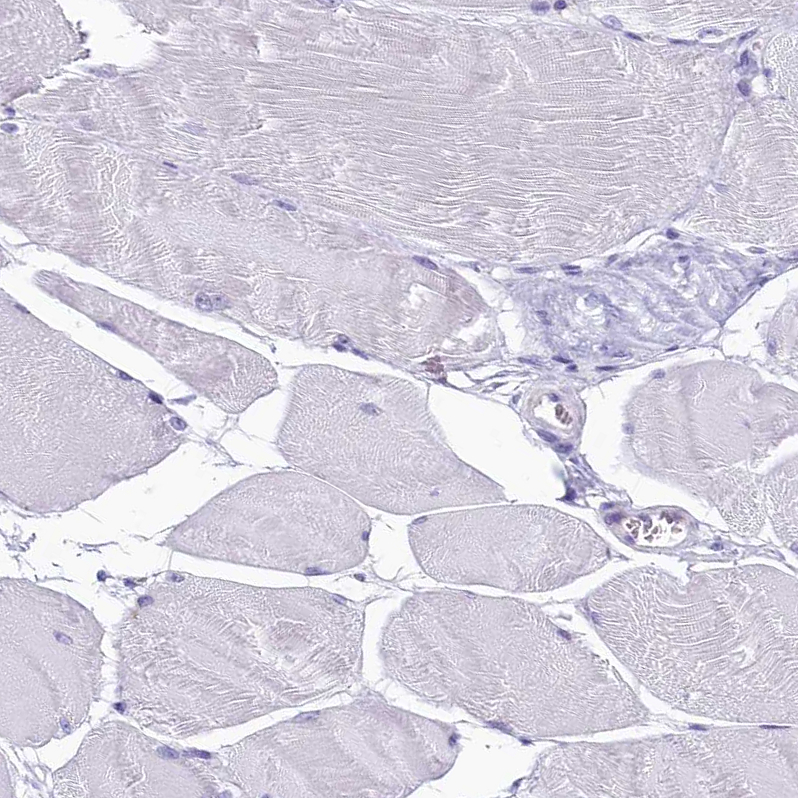

Immunohistochemical staining of human colon shows strong cytoplasmic positivity in glandular cells.